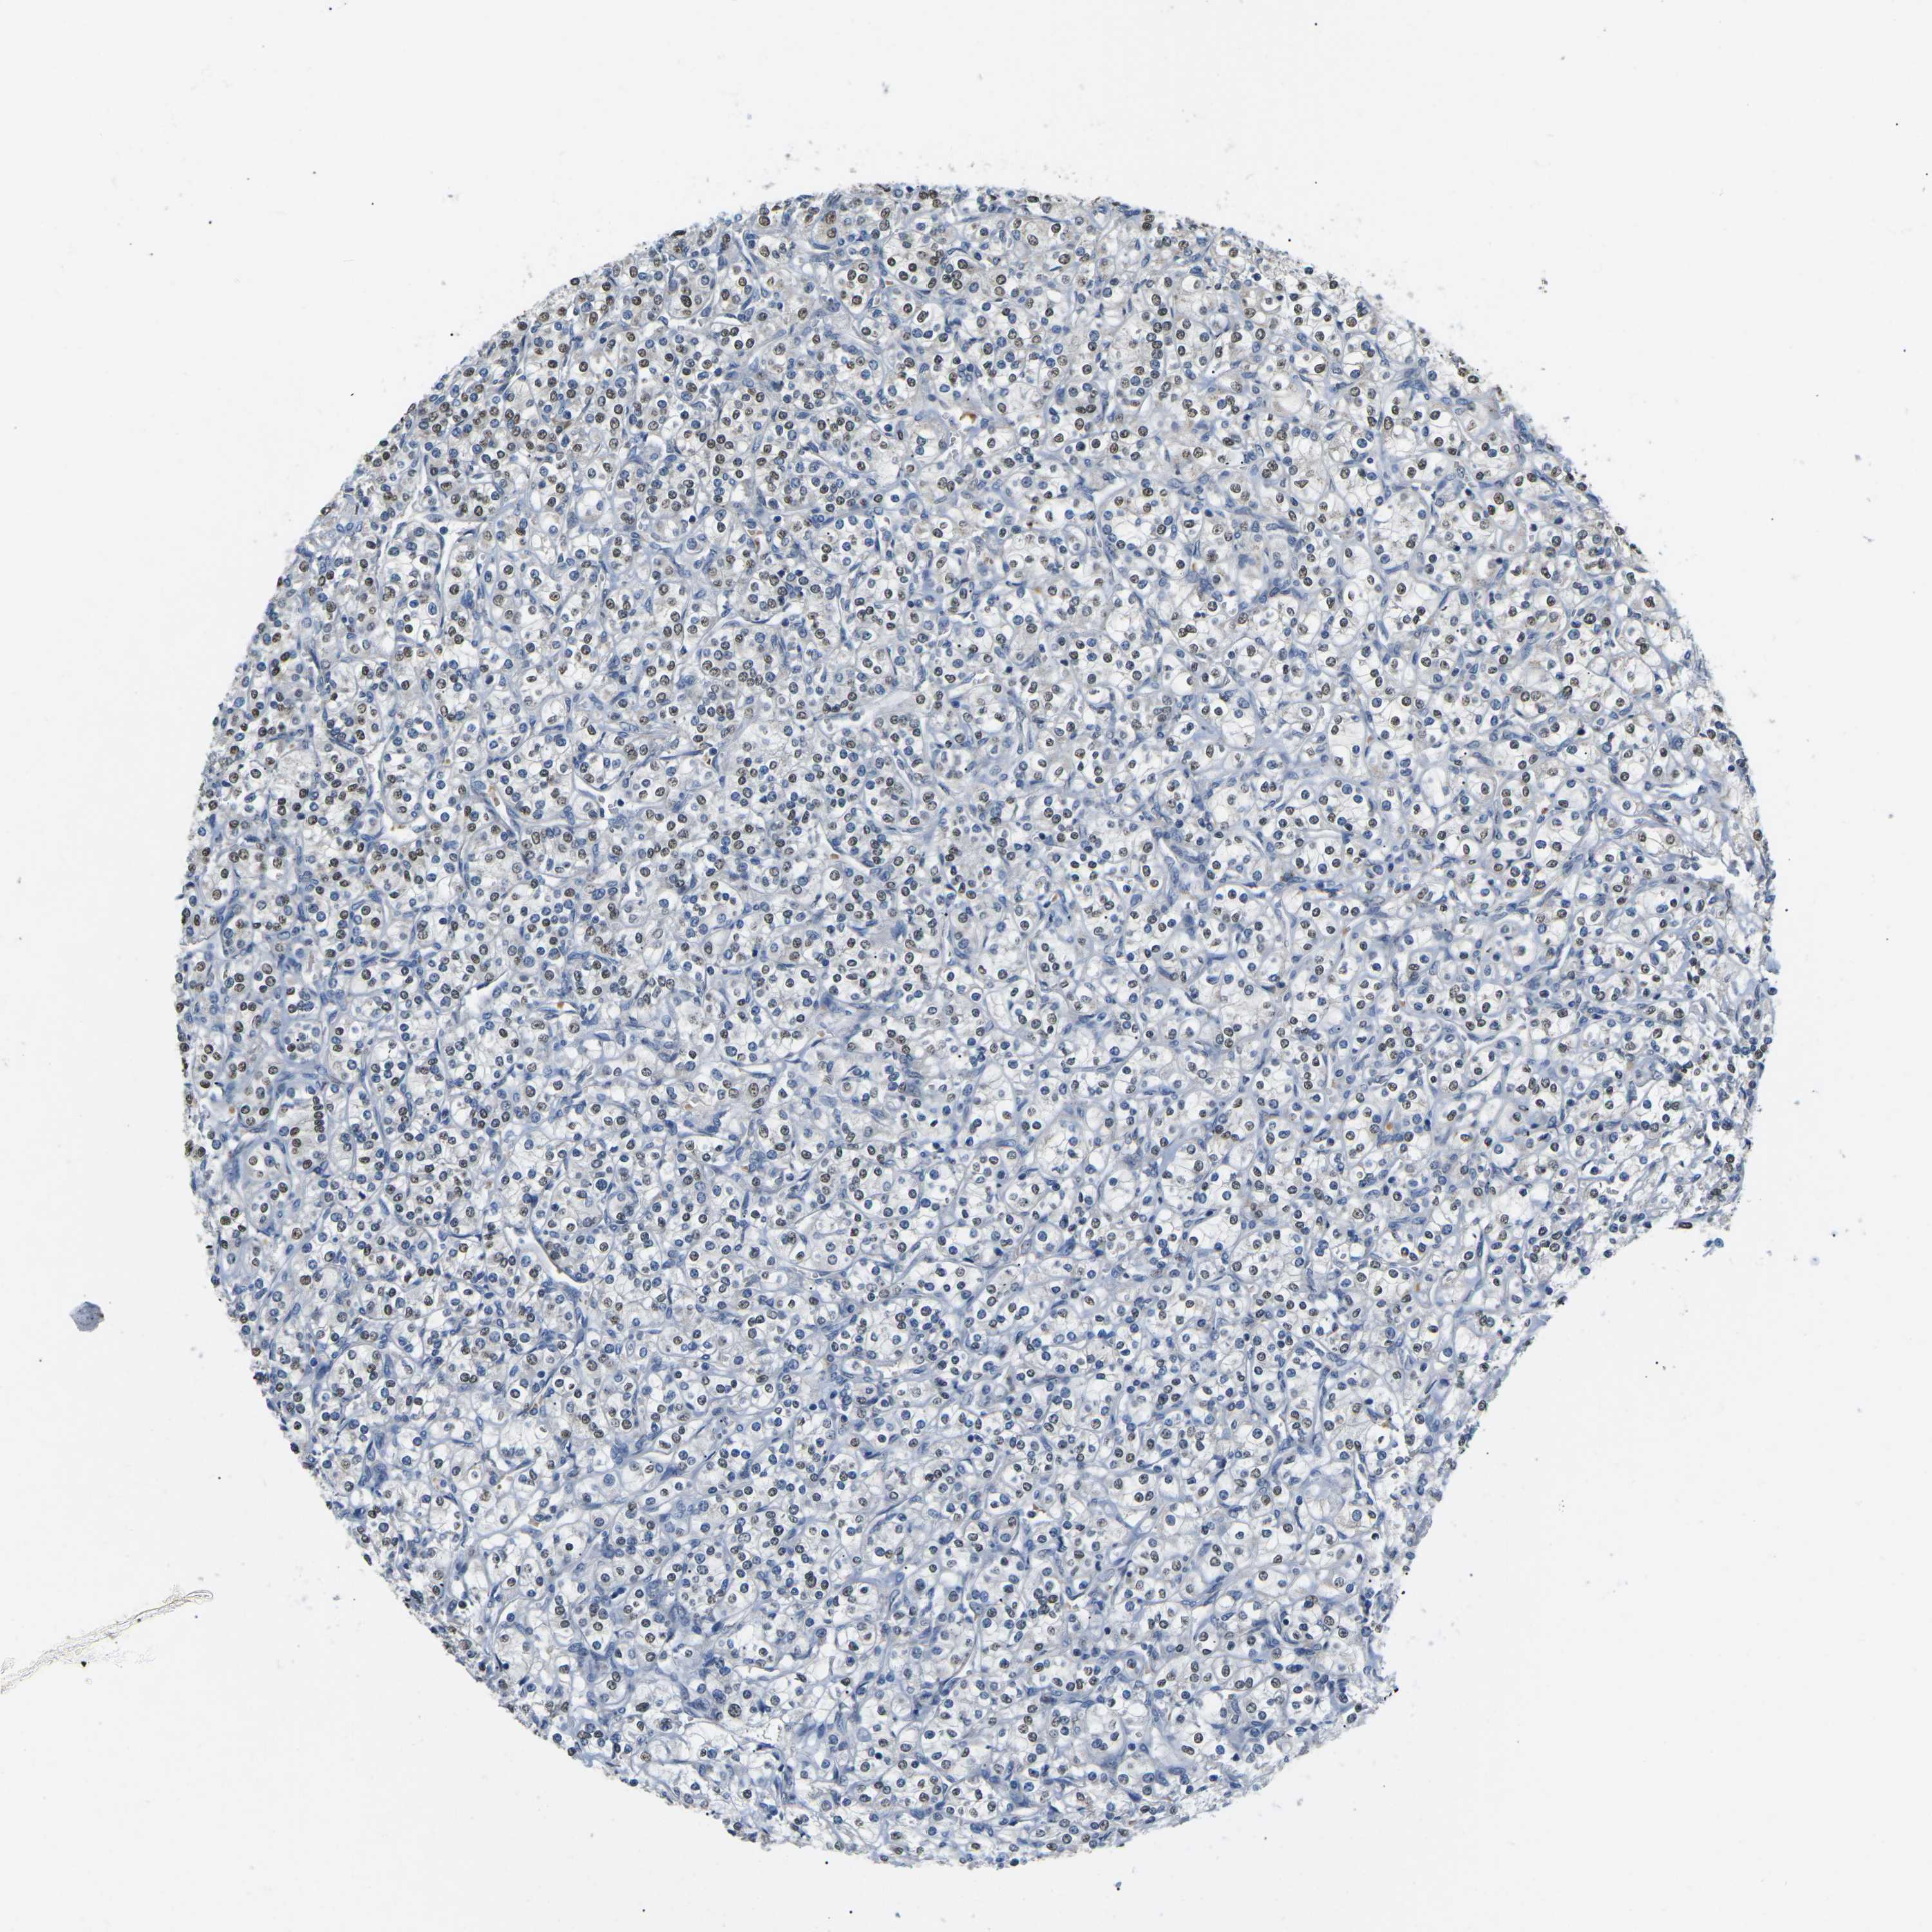

TCGA RNA samplesi

RNA-seq data is reported as average FPKM (number Fragments Per Kilobase of exon per Million reads), generated by the The Cancer Genome Atlas (TCGA) .

Normal distribution across the dataset is visualized with box plots, shown as median and 25th and 75th percentiles. Points are displayed as outliers if they are above or below 1.5 times the interquartile range. FPKM values of the individual samples are presented next to the box plot.

Average pTPM 0.4

Number of samples 521